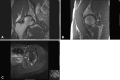

Methods: We reviewed the records of all 22 athletes presenting to our clinics with a posterior acetabular rim fracture confirming a posterior hip instability episode. Radiograph, CT, and MRI findings were documented in all patients. Intraoperative findings were recorded in patients undergoing surgery. There were 19 males and three females with an average age of 22 years (range, 13-31 years). Minimum followup was 2 years (average, 4 years; range, 2-16 years).

Results: The mean modified Harris hip score was 94, Hip Outcome Scores for Activities of Daily Living and Sport were 99 and 87, respectively, and 20 of 22 athletes returned to sport. The most common constellation of pathoanatomy was a posterior labral tear with rim fracture, anterior labral tear, capsular tear, ligamentum teres avulsion, and chondral injury of the femoral head with loose bodies. Sixteen of the 18 patients with femoroacetabular impingement (FAI) had a twisting or noncontact mechanism of injury.